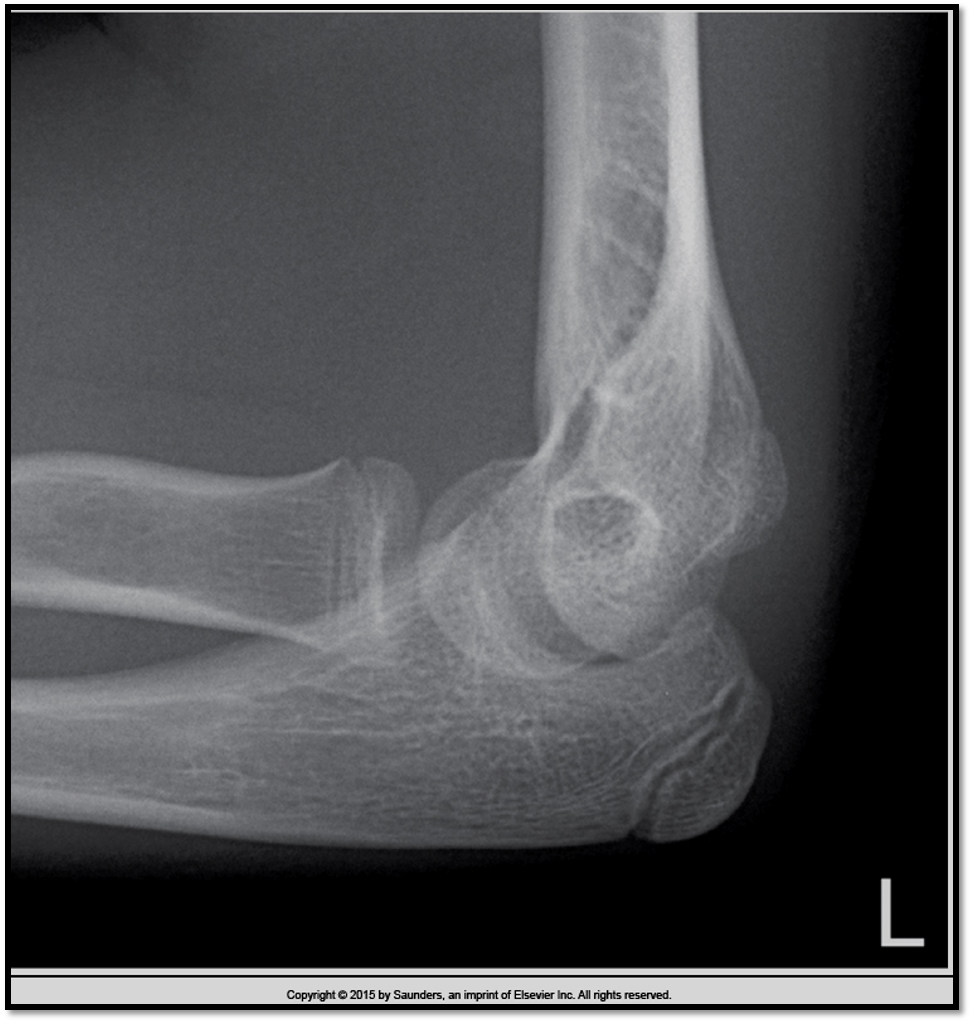

Lateral Elbow Criteria

A

• elbow flexed 90

• capitulum and trochlea superimposed

• articulating surfaces of the radial head and coronoid process are aligned